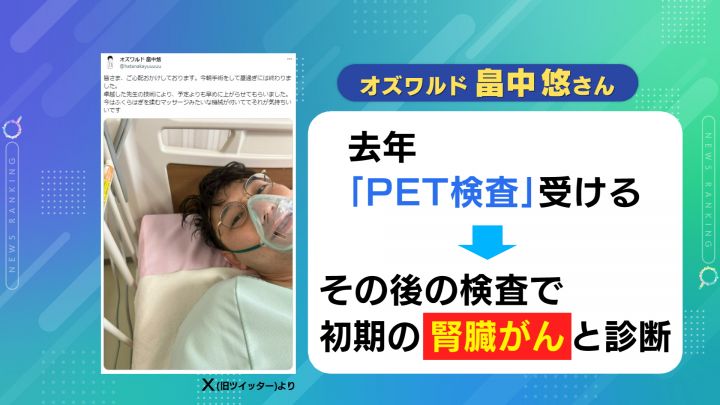

がんの早期発見に注目が集まっています。2024年2月末、お笑いコンビ・オズワルドの 畠中悠(はたなか・ゆう)さんが、 腎臓がんの手術を受けたことを明らかにしました。

2023年、「PET検査」を受けたところ腎臓に腫瘍が見つかり、その後の検査で初期の腎臓がんと診断されたということです。